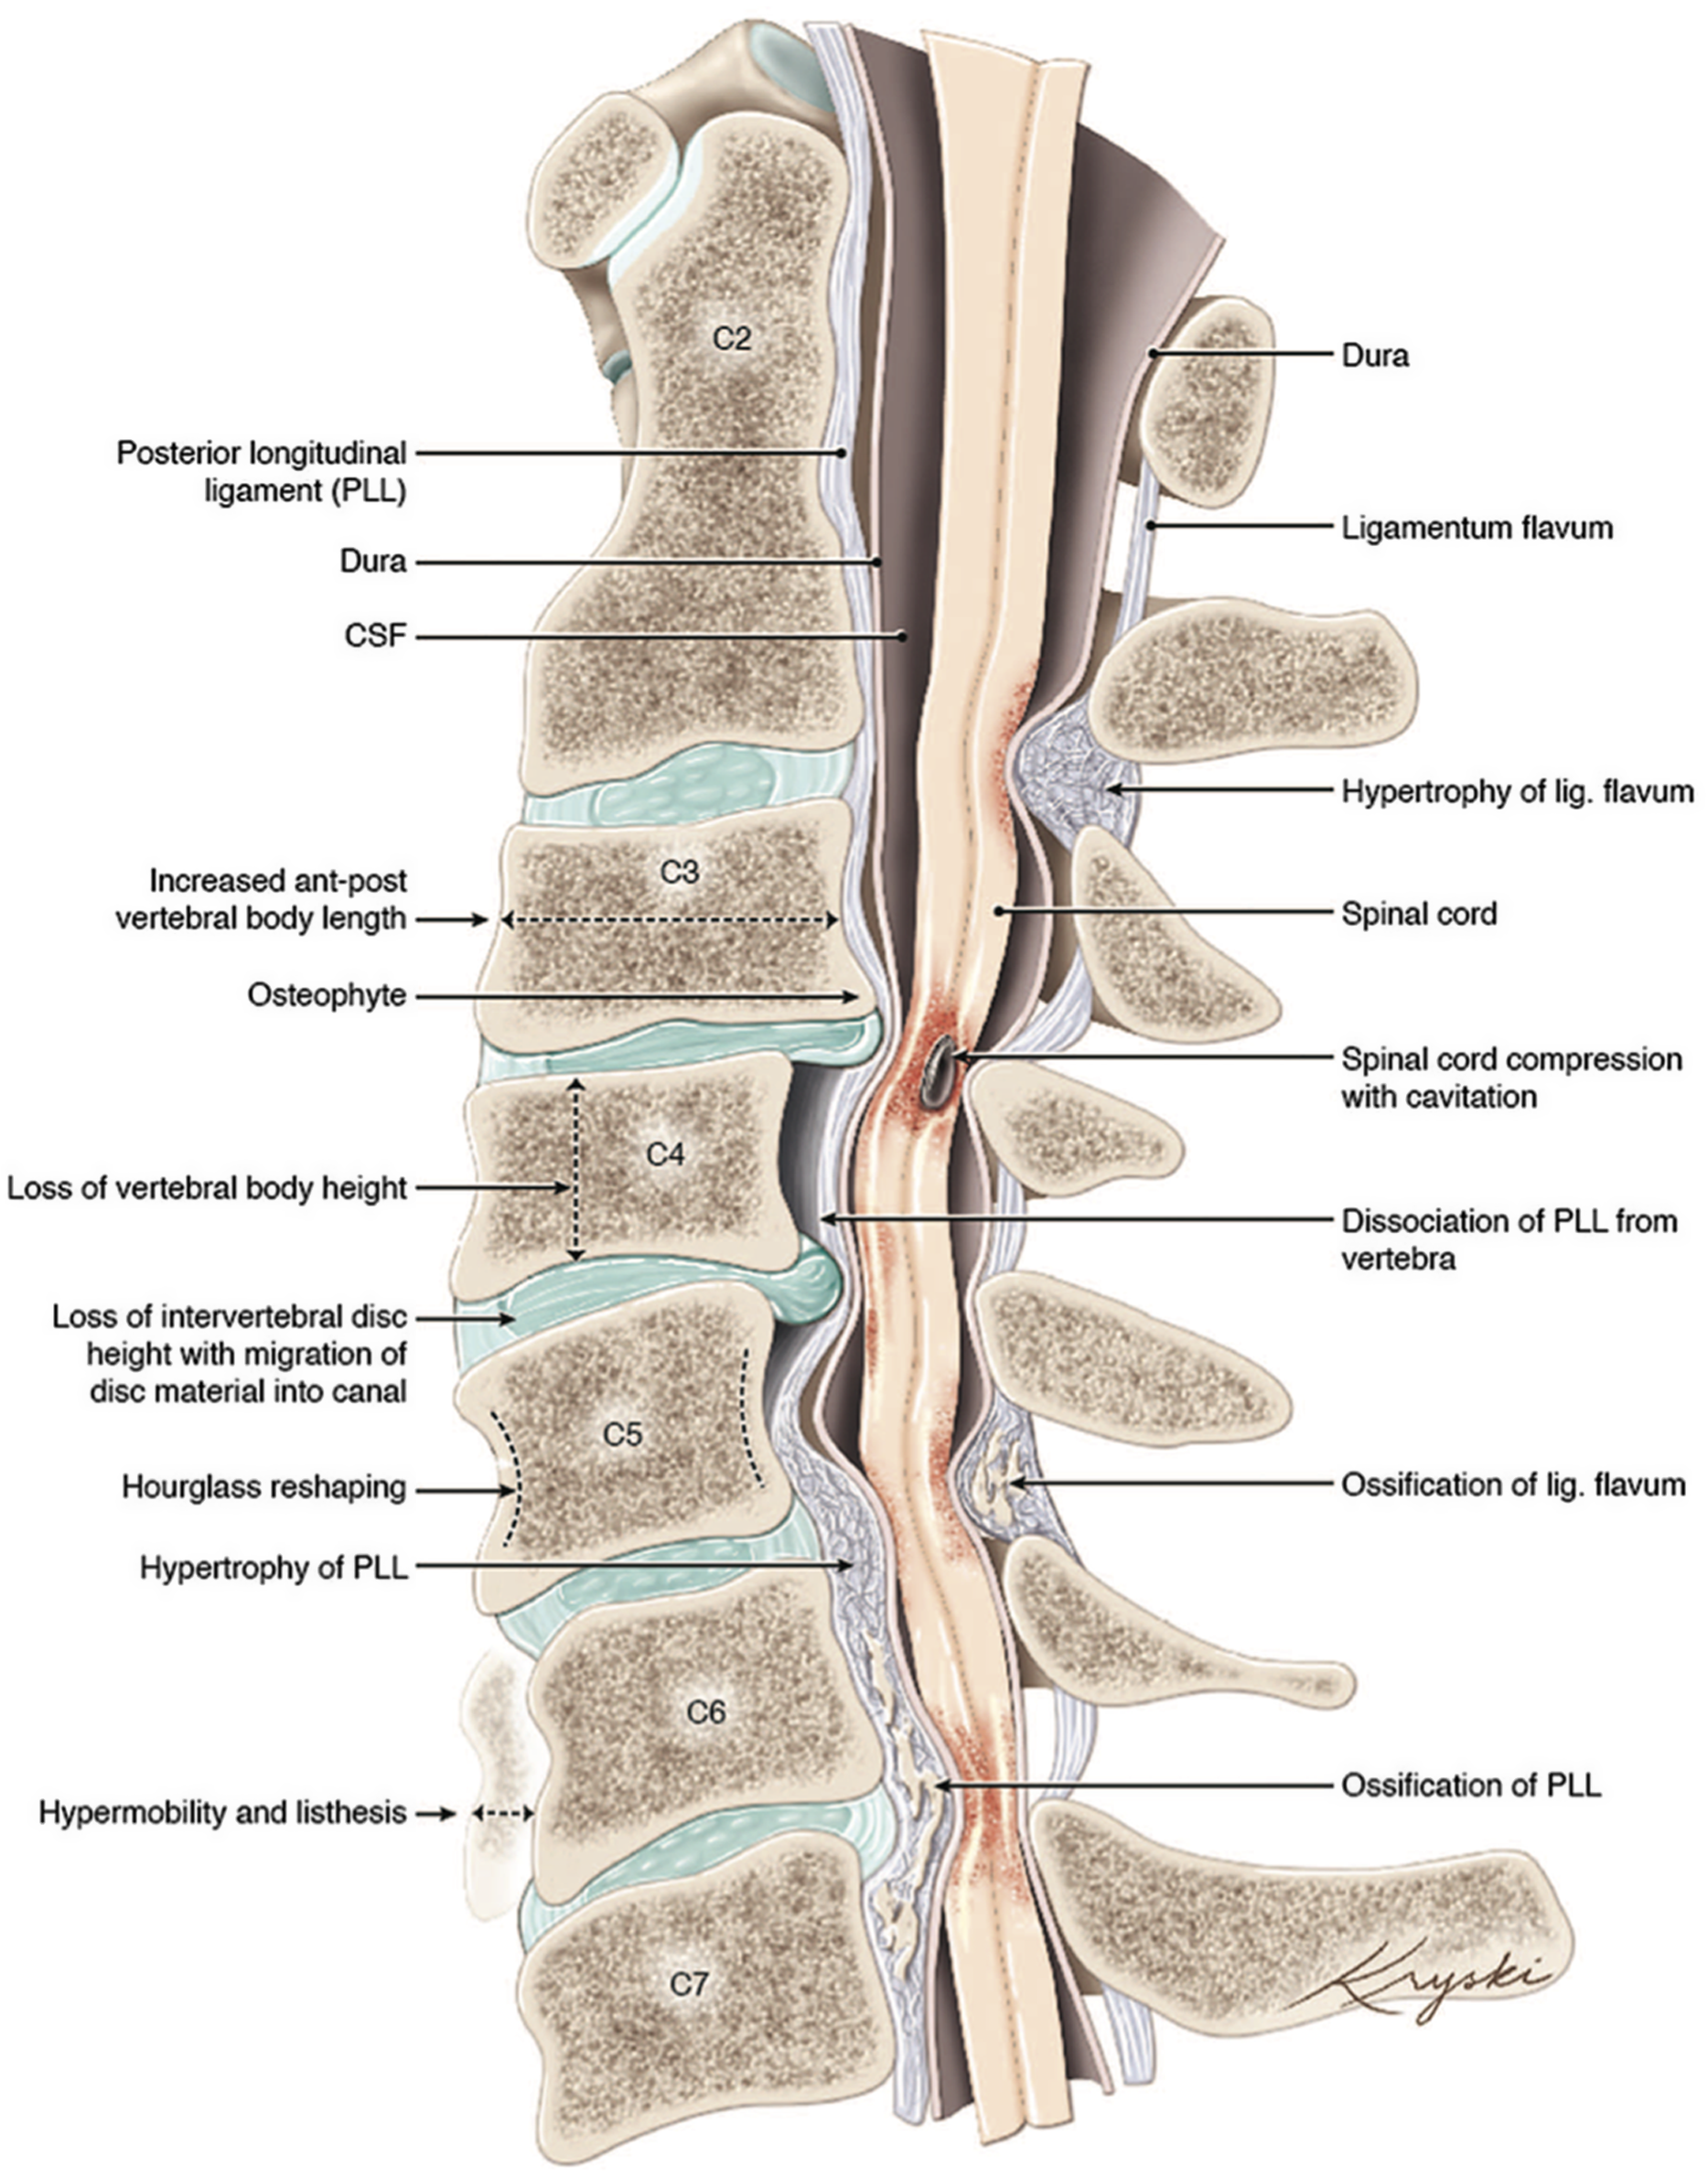

DCM represents an overarching clinicopathological entity encompassing a variety of age-related and genetically associated degenerative conditions of the cervical spinal column including degenerative disc disease (DDD), cervical spondylotic myelopathy (CSM), and ligamentous aberrations including ossification of the posterior longitudinal ligament (OPLL), (Figure 1). Reference Nouri, Tetreault and Singh4 On occasion, congenital disorders including Klippel-Feil Syndrome(KFS) and Ehlers-Danlos syndrome may contribute to the development of DCM. Reference Nouri, Tetreault and Singh4 These eventually culminate in chronic compression of the spinal cord causing neurological compromise through static and dynamic injury mechanisms. In this section, we will outline the clinical entities surrounding the term DCM as well as provide an overview on the pathophysiological mechanisms of chronic spinal cord compression encountered in DCM.

Figure 1: An illustration of the varied anatomical changes in the cervical spine that may underly the development of degenerative cervical myelopathy. Medical illustration by Diana Kryski (Kryski Biomedia). Reprinted with permission from Nouri A, Tetreault L, Singh A, et al. Degenerative Cervical Myelopathy: Epidemiology, Genetics, and Pathogenesis. Spine 2015;40:E675.